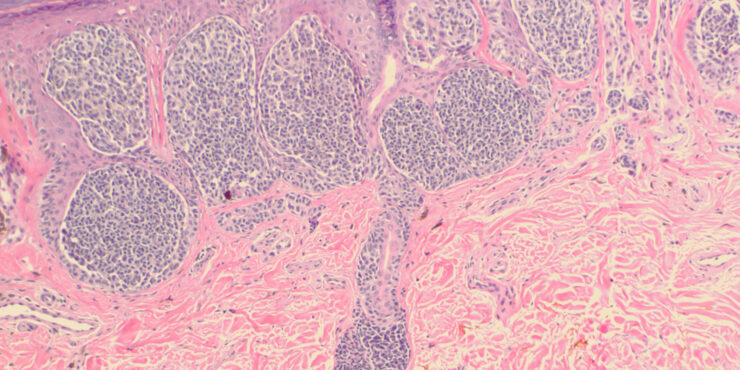

Acquired progressive lymphangioma =الورم الوعائي اللمفاوي المترقي المكتسب